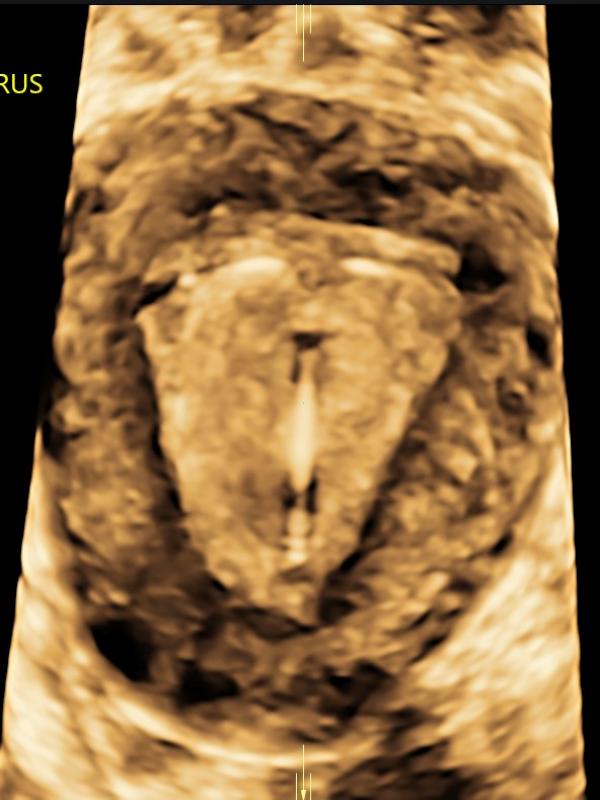

Female Pelvic/Gynecologic ultrasound

A provider may order a pelvic ultrasound for a number of reasons. Some common reasons are: pelvic pain, irregular bleeding, lack of periods or fertility assessment. Ultrasound has proven to be an important diagnostic tool in evaluating the gynecologic patient. With improved technology, ultrasound plays an integral role in evaluating the female pelvis. The uterus, uterine lining (endometrium), and ovaries are well-visualized using transabdominal and transvaginal ultrasound imaging.

- What should I expect during this exam? Typically, your provider will order a transabdominal and transvaginal ultrasound to evaluate the uterus, uterine lining and ovaries. Transabdominal (ultrasound performed by placing the transducer on the skin of the lower abdomen). Transvaginal (ultrasound performed by placing a cylinder-shaped ultrasound camera into the vagina). Transvaginal ultrasound adds information and is often the preferred method of evaluation.